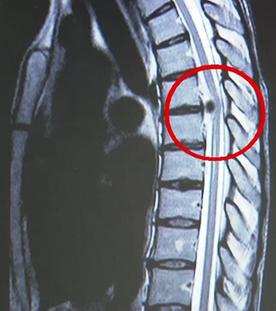

Die Themen der Sendung:Übergewicht bei Kindern: Die Ernährung in den ersten 1.000 Tagen ist entscheidend.Weltweit gibt es immer mehr übergewichtige Kinder. Laut dem Robert Koch Institut gelten hierzulande fast 15 Prozent der Kinder und Jugendlichen als zu dick. Experten gehen davon aus, dass die Anlagen für die Neigung zum Übergewicht schon sehr früh gelegt werden. Konkret: bereits im Mutterleib und in den ersten Lebensjahren. Lebensstil und die richtige Ernährung von Mutter und Kind spielen demnach eine gewichtige Rolle. Doch auch in der weiteren Entwicklung kann man aktiv gegensteuern. "Gesundheit!" stellt spezielle Angebote für Eltern und Schulen vor, die dabei helfen, Kinder gesund durch den Alltag zu bringen. Bandscheibenschäden der Brustwirbelsäule: Warum sie oft lange nicht erkannt werdenDiese Symptome können auf ganz verschiedene Krankheiten hindeuten: Schmerzen im Brustbereich oder entlang der Rippen, beim Bewegen der Arme, beim Husten und Lachen, Gefühlsstörungen oder sogar Lähmungserscheinungen. Steckt eine Borreliose, Gürtelrose, Lungenerkrankung oder ein Tumor hinter diesen Beschwerden? Der Weg zur Diagnose „Bandscheibenvorfall an der Brustwirbelsäule“ ist oft eine Odyssee. "Gesundheit!" zeigt, in welchen Fällen dann eine konservative Behandlung genügt, und warum eine Operation an der Brustwirbelsäule besonders heikel ist.Erythrophobie: Angst vor dem ErrötenOft passiert es ausgerechnet in Situationen, in denen es am wenigsten passt: bei einer Präsentation im Beruf, beim Gespräch mit dem Chef, bei einer Prüfung oder einem Date. Das Blut steigt in den Kopf, das Gesicht wird warm, die Gedanken kreisen nur noch um die glühenden Wangen. Rotwerden ist unangenehm, doch manche Menschen entwickeln eine regelrechte Panik davor. Wenn man aus Angst vor dem Erröten andere Menschen meidet oder nicht mehr aus dem Haus geht, ist die Schwelle zur Erkrankung überschritten. Erythrophobie heißt die Angst vor dem Erröten. "Gesundheit!" hat die 17-jährige Svenja getroffen, bei der die Angststörung so schlimm war, dass sie nach ihrem Schulabschluss sogar den Kontakt zu Freunden abgebrochen hat. Haare: Was verraten sie über unsere Gesundheit?Rund drei Millionen Euro geben die Deutschen jährlich für Haarpflege aus. Tendenz steigend. Schöne, gesunde Haare sind den meisten ziemlich wichtig. Ob unkomplizierter Kurzhaarschnitt oder Lockenmähne, ob praktisch oder aufwendig frisiert – unser Kopfschmuck sagt viel über unsere Persönlichkeit aus. Aber was verraten die Haare über unsere Gesundheit? Speichern sie die Umwelt- und Lebensbedingungen? Diesen Fragen geht der Reporter Fero Andersen nach – bei einem Friseur, einer Dermatologin und einer Kriminalbiologin.